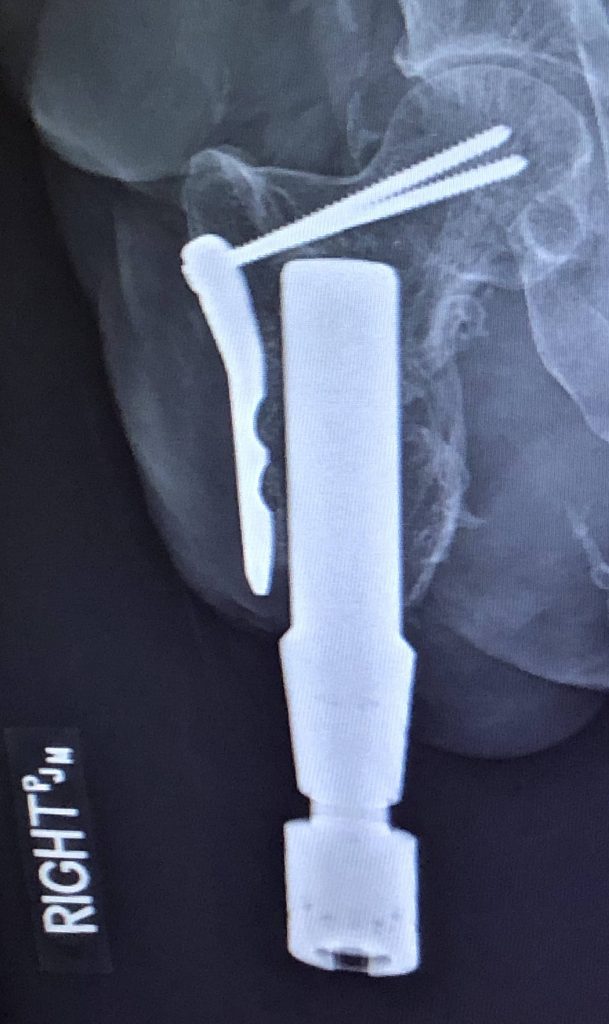

Osseointegration Limb Replacement

After a traumatic car accident in 2016, I lost my right leg. I was only left with a few inches of my femur. In total I have had 28 surgeries since the accident. I was unable to walk using a traditional prosthetic socket, which meant that I only walked using forearm crutches for 4 years. I had been researching osseointegration surgery for a few years, and assumed I would have to travel overseas to get it. This was my only chance to walk again. In order to prepare for the surgery, I had 3 surgeries prior to lengthen my small femur. Even after bone lengthening, my femur was only around 3.5”. I was lucky enough to read about Dr. Rozbruch just around the time I was getting more serious about going overseas for surgery. He had been trained using the press fit implant that I wanted to get. We drove to NYC for a consultation. Not only was he willing to take on the challenge, everything felt just right. It’s important to be able to put faith in your surgeon, and I knew that would not be a concern. Leading up to my osseointegration surgery on 11/15/19, both Dr. Rozbruch and I decided to be brave knowing the risk involved. The risk, patience, and rehab after osseointegration have given me the reward of walking again. It has now been just over a year, and I am walking unassisted. I use a cane for longer walks. I wake up every morning grateful that I wrote that email to ask if he could help me. Dr. Rozbruch and HSS have given me so much independence back, and a fresh start! Thank you from the bottom of my heart.